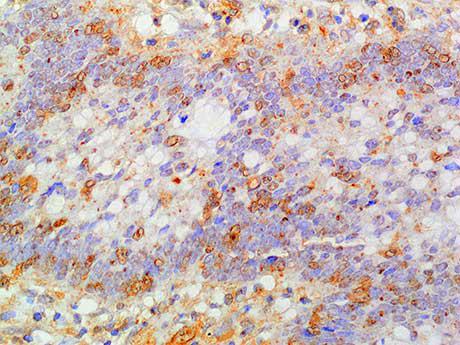

Smad1 belongs to the Smad family, which is a protein family of gene products similar to Drosophila genes, such as "Mother Against Peeling" (MAD) and the Caenorhabditis elegans gene SMA. One of the most important proteins regulating TGF - β ligand activity is the SMAD family of proteins. SMAD1 is one of the receptor activated Smads. It is also a signal transducer for BMP signaling and binds to several proteins involved in the ubiquitin proteasome system (UPS). It mediates the signaling of bone morphogenetic protein (BMP), which is involved in a range of biological activities including cell growth, apoptosis, morphogenesis, development, and immune response. In response to BMP ligands, Smad1 can be phosphorylated and activated by BMP receptor kinase. Its phosphorylated form forms a complex with Smad4, which is important for its function in transcriptional regulation.